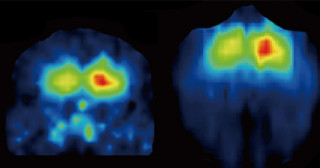

カルビンディン遺伝子の導入によりドーパミン細胞死の防御に成功 -パーキンソン病の発症・進行を抑える新たな治療法の開発に期待-